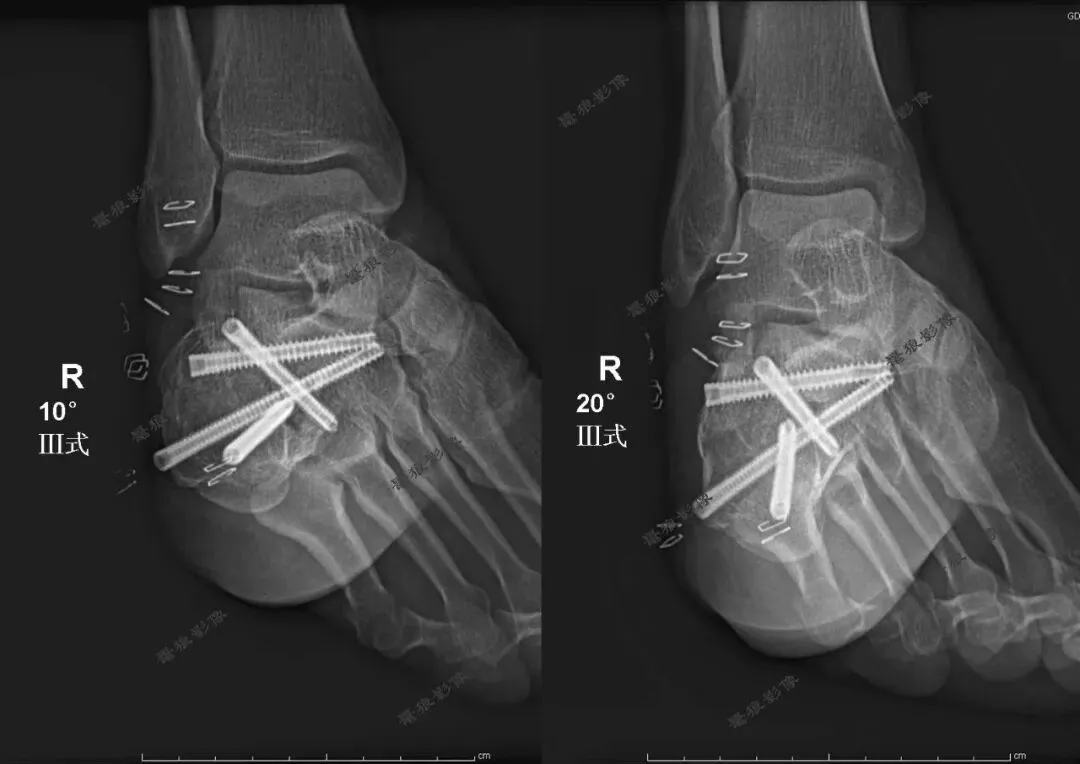

【学习笔记】跟骨Broden位(Ⅲ式)的临床应用